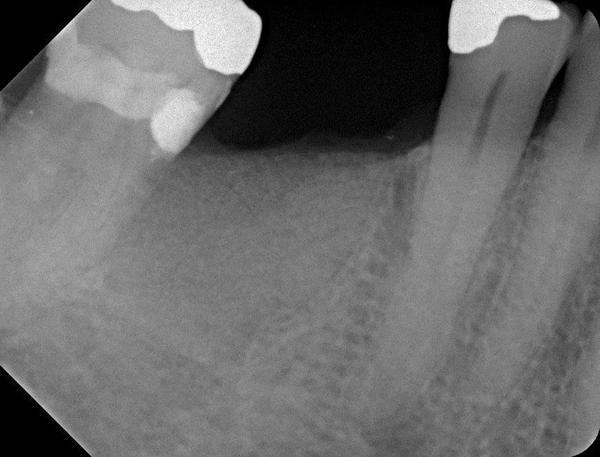

Fig 15. (Case 3) Radiograph of tooth No. 19, which had a hopeless prognosis.

Figure 15

Fig 16. Radiograph of extraction socket. Buccal and lingual plates were defective.

Figure 16